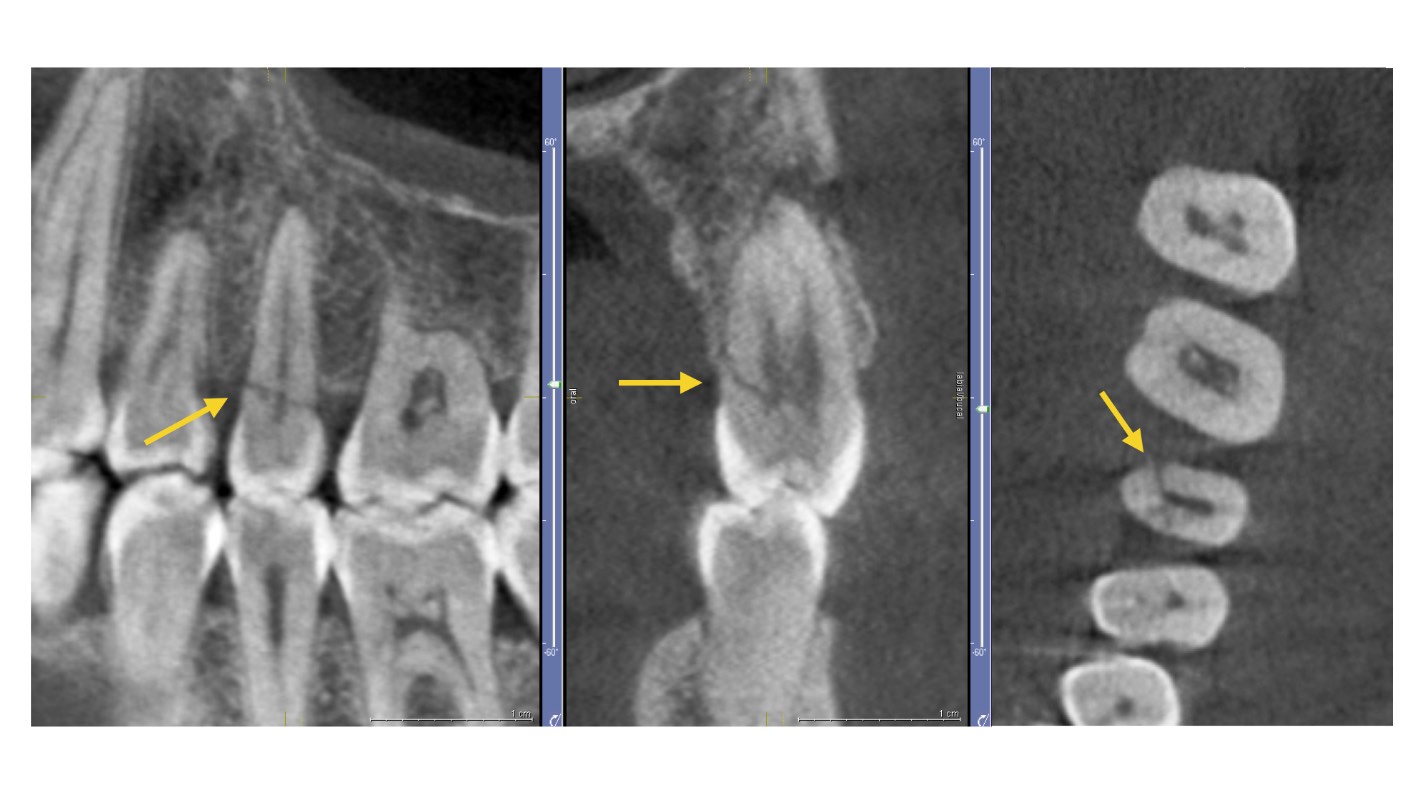

If your field of work is endodontics, a CBCT scanner can provide the axial, coronal and sagittal view that you can't achieve with conventional radiology, although conventional radiology is certainly more practical and suitable for the most common endodontic procedures. CBCT has a great advantage in eliminating or reducing the overlapping of structures, for example, for:

Visualising root canal anatomy: if you use a CBCT scanner with a limited FOV you can more accurately recognise root canals and provide more accurate measurements of root angulations.

Identifying periapical pathology: with a CBCT scanner you could obtain greater sensitivity in the diagnosis of experimental periapical lesions, however, we must not forget that artefacts from restorative materials could hinder the diagnosis.

Identification of tooth fractures: the CBCT scanner outperforms conventional radiology in the diagnosis of tooth fractures because unless the beam is oriented so that it passes through the fracture plane, it is not possible to separate the fragments on an intraoral radiograph. Again, this diagnosis on CBCT may be impaired by artefacts.

Analysis of the internal and external root reabsorption process: with your CBCT scanner you can not only detect the exact location, but also determine the extent of the reabsorption and the communication with the periodontal ligament space.